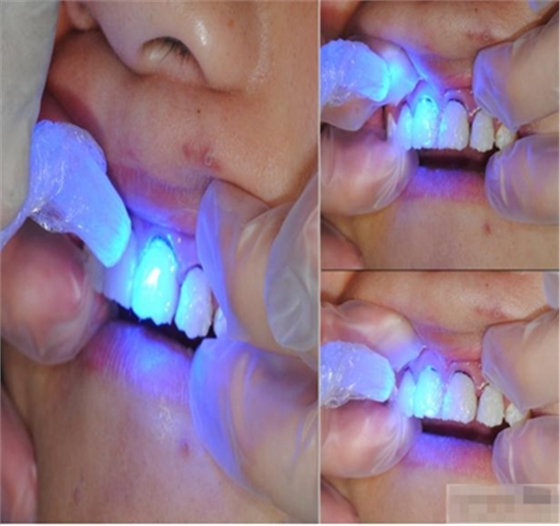

【酸蝕粘結(jié)】

使用磷酸酸蝕可用完全去除玷污層,粘結(jié)劑可用充分滲透到牙本質(zhì)小管中。用自酸蝕系統(tǒng)則達(dá)不到這一點(diǎn),由于其不能充分去除玷污層,粘結(jié)劑向牙本質(zhì)小管內(nèi)的滲透率低。所有的研究均顯示,使用全酸蝕系統(tǒng)所形成的粘結(jié)混合層要比使用自酸蝕系統(tǒng)厚。

將粘結(jié)劑在牙體硬組織上充分涂布20秒,最少2次,然后,輕輕吹干,固化。理想的粘接劑的厚度不應(yīng)超過50微米。如果粘接層過后可能會(huì)發(fā)生微滲漏,過薄則可能彈性不足。飽和粘接系統(tǒng)第一層厚度可以達(dá)到30-40微米,有時(shí)也會(huì)超過此值。但這個(gè)厚度對(duì)于一些情況不適用,如嵌體粘結(jié)。80-100微米厚度的粘接層難以形成持久的固位力。電子顯微鏡照片顯示飽和粘接系統(tǒng)會(huì)形成較厚的粘接層,并且,其內(nèi)部充滿氣泡,optibond和PQI就屬于飽和粘結(jié)系統(tǒng)。Dr.Vanini的建議最好使用不飽和粘結(jié)系統(tǒng),因?yàn)椋柡驼辰Y(jié)系統(tǒng)往往會(huì)形成過厚的粘結(jié)層。Dr.Vanini使用ENA bond粘接系統(tǒng),在單層應(yīng)用時(shí)厚度為8微米,2層為12微米,3層為25微米。三層粘結(jié)劑所形成的粘接力值可以達(dá)到49MPa(N/平方MM)。使用非飽和粘結(jié)系統(tǒng)進(jìn)行2-3層的粘接方法的另一個(gè)優(yōu)點(diǎn)是可以減少術(shù)后過敏癥狀的出現(xiàn)。

紙尖拭干

光照強(qiáng)度要達(dá)到800-1000毫瓦。鹵素?zé)舻拇┩噶σ劝l(fā)光二極管強(qiáng)。粘結(jié)嵌體時(shí)要用鹵素?zé)?。常?guī)應(yīng)用發(fā)光二極管燈更加方便。